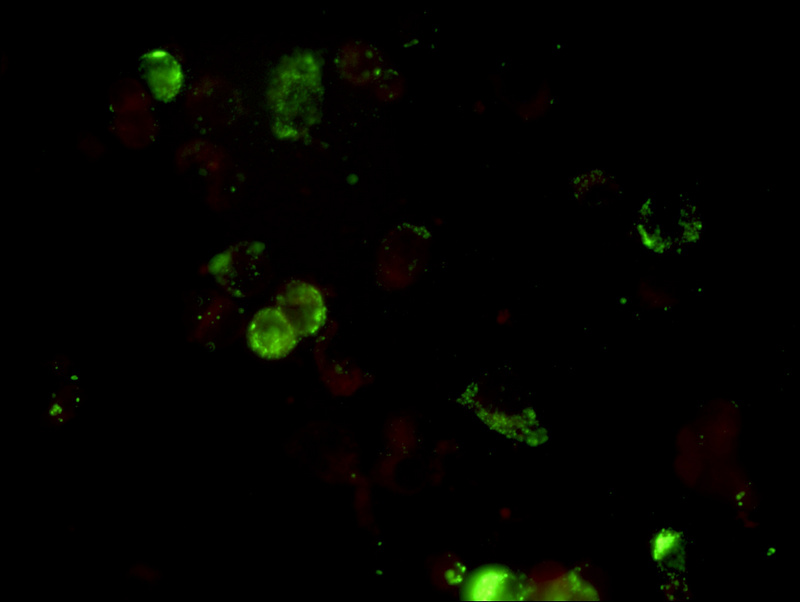

流感疫苗_13.jpg

MF31拍摄的流感病毒免疫荧光检测

流感疫苗_06.jpg

流感病毒检测阴性

使用荧光显微镜400倍视野观察(40X物镜),甲型流感检测孔位荧光少且弱,视为阴性结果,荧光亮度强数量多,平均每个视野的阳性细胞大于3-5个,就可以判断为阳性。乙型流感另有一个孔位,判断标准和甲型流感一致。

流感疫苗_07.jpg

流感病毒检测阳性